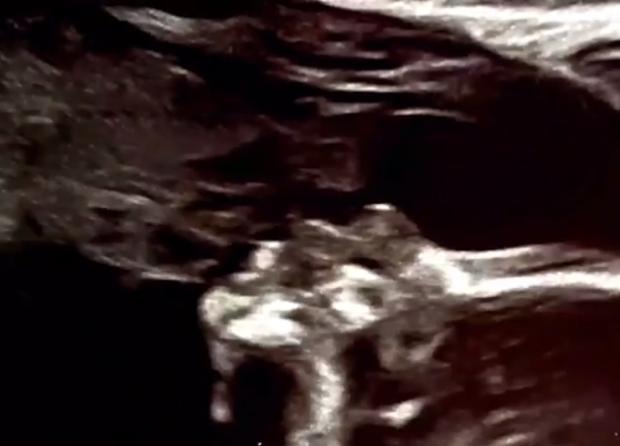

近日,香黛儿在社交媒体上发布了自己怀孕20周的B超图,她的朋友们在这张图上看到了神奇的一幕。

香黛儿说:“我刚把图片放在网上大概30秒后,有一个朋友给我留言说,‘有个天使在亲吻你的宝宝!’老实说,这个消息让我既意外又吃惊,于是我又仔细看了看这张图,竟真的看到了我已逝的父亲在亲吻我女儿。”

照片中,孩子的头顶上有一个清晰可见的轮廓,神似十年前香黛儿的父亲查克,抱着她的第一个女儿麦莉·帕切科的照片。当时,查克戴着一顶红帽子,认真地望着那个婴儿。

香黛儿拿着超声波说:“照片里可以看到我爸爸独特的鼻子、脸颊。你看,这是他下巴上鼓起的小圆球,我爸爸的下巴长得很特别。”